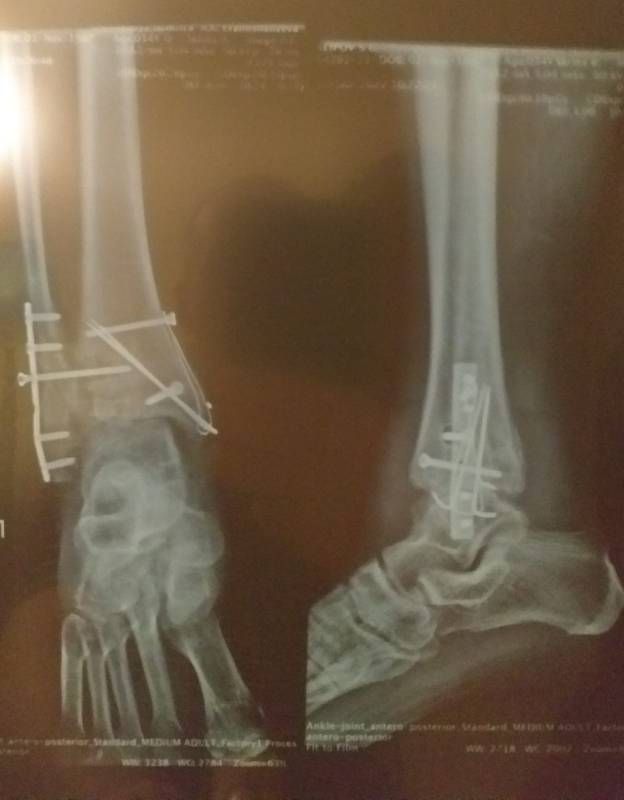

oxana(vogel), нет нет у меня перелом правого голеностопного сустава со смещением был. Установили металлоконструкцию. Через год ее сняли И сейчас Артроз 3 стадии в следствии травмы! Изображение

oxana(vogel), через года сняли железо так вот! Изображение Изображение